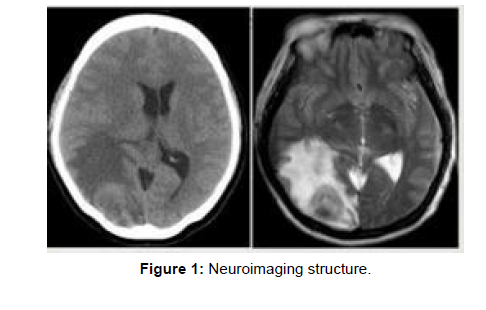

Neuroimaging is the utilization of quantitative (computational) methods to concentrate on the design and capability of the central nervous system, created as an objective approach to logically concentrating on the healthy human brain in a non-invasive manner [1,2]. Progressively it is likewise being utilized for quantitative investigations of brain disease and psychiatric illness. Neuroimaging is a profoundly multidisciplinary research field and is not a medical specialty (Figure 1).